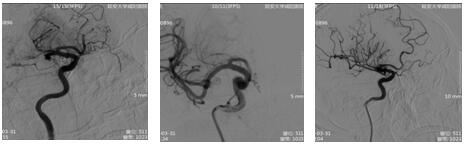

17:21 DSA示:右侧大脑中动脉、前动脉闭塞。与患者家属谈话,签字后立即行中动脉、前动脉取栓术。